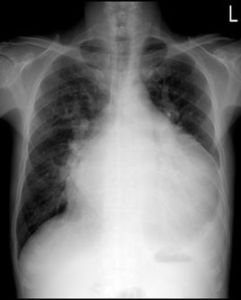

正常人頸靜脈不擴張,或施壓之初可有輕度擴張,但迅即下降到正常水平。右心衰竭者則明顯怒張,但於停止壓迫肝臟後迅即下降,(至少4CM水柱)為陽性。

囑患者臥床,頭墊高枕,張口呼吸,避免憋氣動作,檢查者右手掌面輕貼於肝區,逐漸加壓,持續10秒鐘,同時觀察頸靜脈怒張程度。檢查時閉口,憋氣,將影響結果判斷。